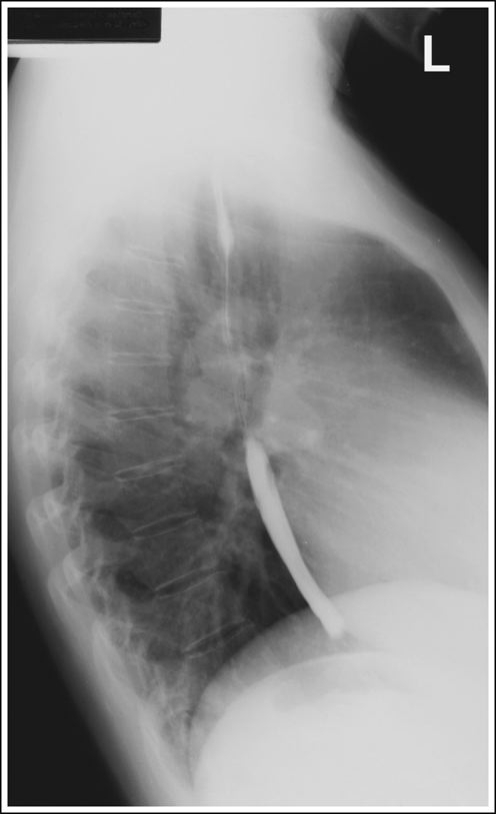

Lateral Esophagus (Right or Left (CR and Positioning)

Recumbent lateral position - preferably right lateral and facing radiographer

Arms forward

MCP centered

Shield patient

Place IR at the top of the mouth

CR at the level of T5-T6

Instruct patient to take big swallows and expose while esophagus is full of barium

Lateral Esophagram Eval Criteria

Arm not interfering with esophagus

Ribs posterior to the vertebrae superimposed with no rotation

Lateral esophagus with proper positioning

Lateral esophagus with superior and middle no barium